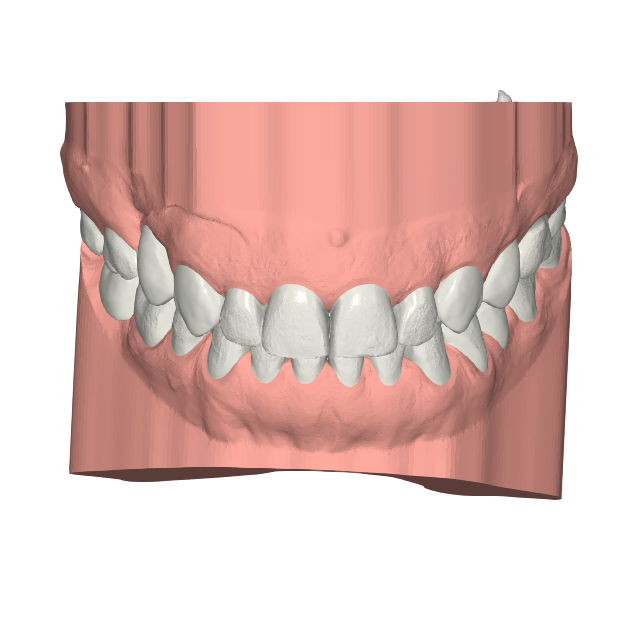

Elevantia Solutions accepted the challenge by designing a treatment plan with Ortho Root Plan Design, a tool that allows orthodontic planning based on the exact position and movement of roots during treatment. This is essential for complex cases because it reduces risks, prevents root damage, and ensures maximum predictability

Ortho Movements

The proposed design corrected midline discrepancies, improved occlusion, and established the foundation for future restorative work. Thanks to this advanced approach, the treatment was safer, more conservative, and highly predictable, providing security for the doctor and confidence for the patient